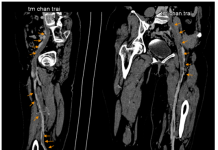

Tổng quan y văn về hội chứng May–Thurner và ca lâm sàng minh họa...

Hội chứng May-Thurner (MTS) là một biến thể giải phẫu...